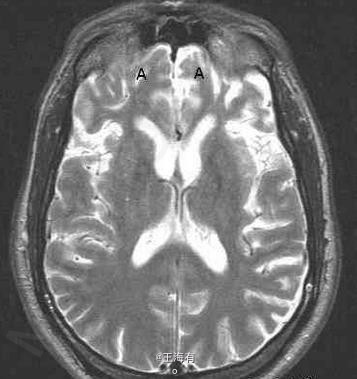

49岁,男,进行性行为改变入院

进行性智能减退,记忆障碍明显

Pick病 处理 此病暂无有效疗法

Pick病是一种罕见的进行性变性疾病,大多累及额叶和颞叶。预后本病预后不良。常在发病1年内迅速转入痴呆